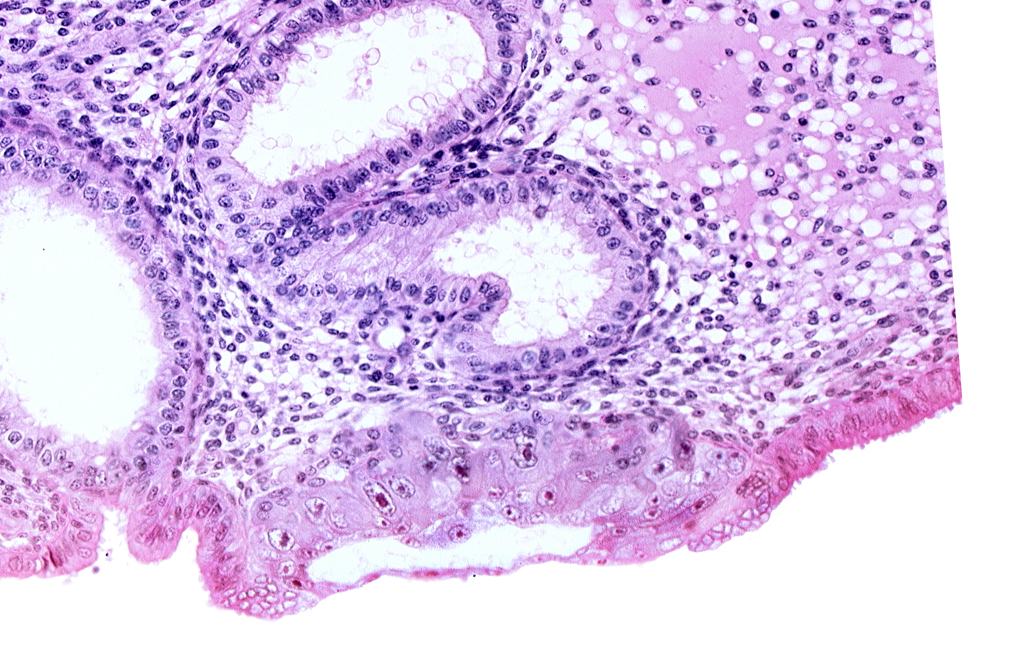

Carnegie Embryo #8020 | Location: 06-03-01

Keywords: blastocystic cavity (blastocoele), cytotrophoblast, edge of amniotic cavity, edge of embryonic disc, lumen of endometrial gland, membranous trophoblast at abembryonic pole, solid syncytiotrophoblast

Source: The Virtual Human Embryo.